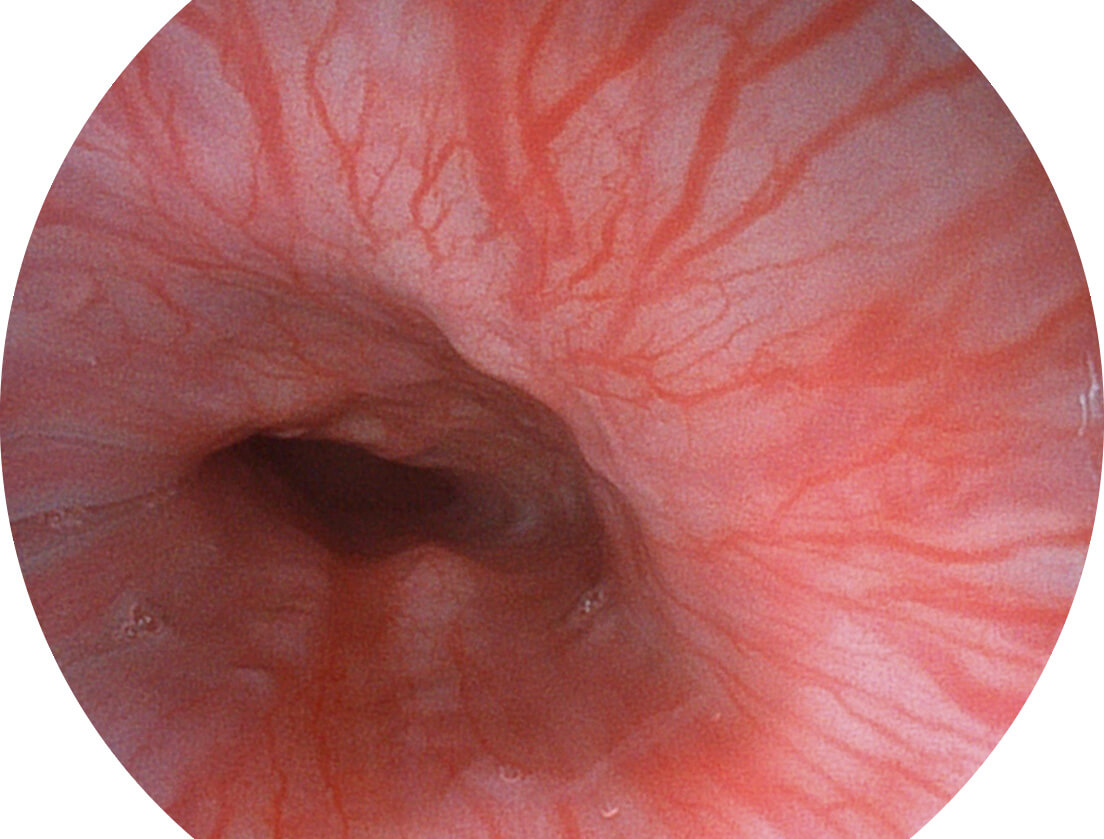

Spectral Focused lmaging, SFI

图像具有高亮度、高黏膜血管颜色对比度的特点,且不改变粘液、食物残渣、粪便的基本颜色,可在中远景下进行观察,助力消化道早期疾病的诊断。

白光图像

SFI图像